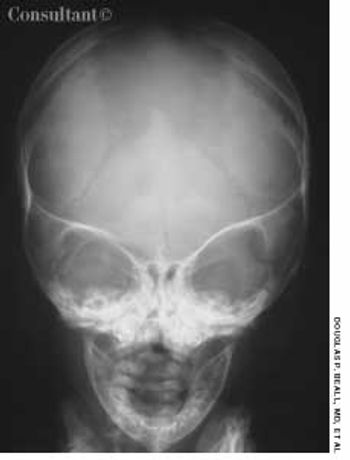

An 80-year-old man with a history of congestive heart failure, coronary artery disease, cardiomyopathy, and thoracic and abdominal aneurysms was taken to the emergency department because of mental status changes, back pain, and ecchymotic areas over his body. The ecchymoses started on his back 5 days before admission and spread to his abdomen.